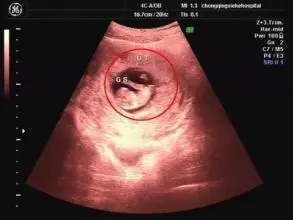

怀孕50天,看胎囊是什么形状50天男孩胎囊形状图片